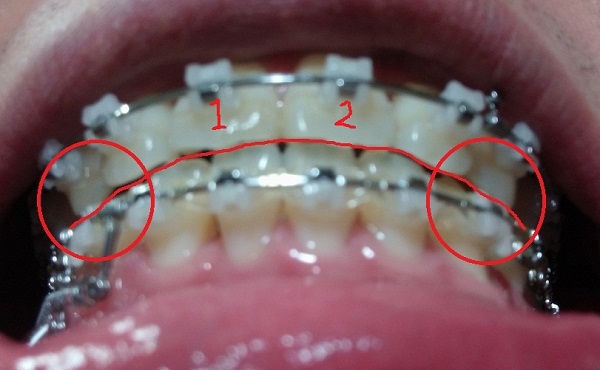

-하악 파워체인 엇갈려서 걸어놓기(후기 23화와 같은 치료),

-하악 파워체인으로 치아끼리 꽉 조여서 마무리로 가는 중!!

[아래서 본 정면1]

[아래서본 정면2]